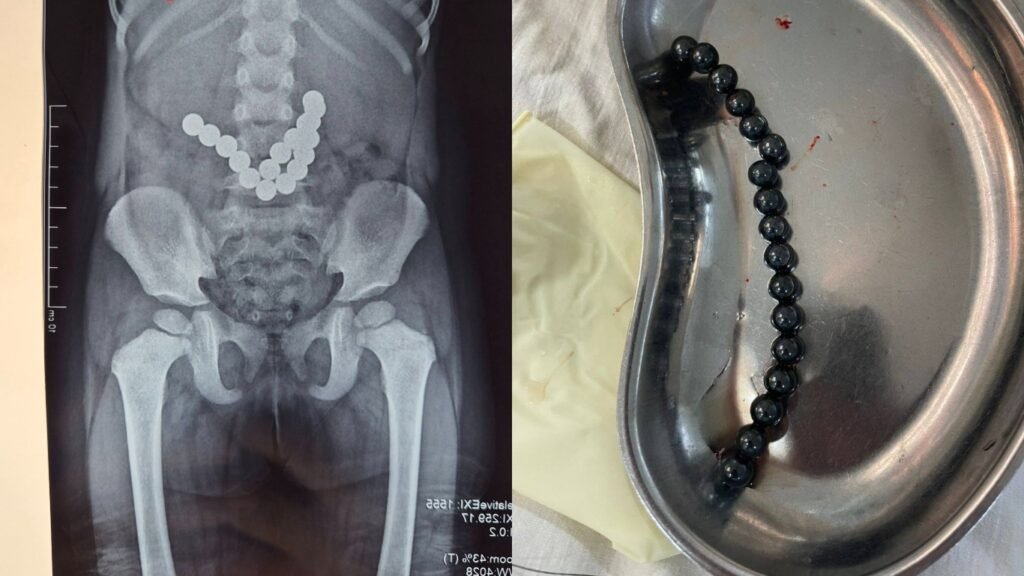

17 магнит жутуп алган. Ошто 2 жашар балага операция жасалды

Ошто оюнчуктун магнитин жутуп алган 2 жаштагы наристеге операция жасалды. Бул тууралуу Ош облустар аралык балдар клиникалык ооруканасы билдирди.

Маалыматка ылайык, наристе 3 күн бою улам-улам кусуп жаткандыктан ата-энеси ооруканага кайрылган. Рентген менен текшерүүнүн жыйынтыгында, баланын ичегилеринде бир нече бөтөн зат бар экени аныкталган. Дарыгерлер шашылыш түрдө операция жасашып, 17 даана оюнчук магнитин алып чыгышкан.

“Учурда бейтаптын абалы туруктуу, тиешелүү дарылоо жана көзөмөл жүргүзүлүп жатат”- деп билдирди оорукана.